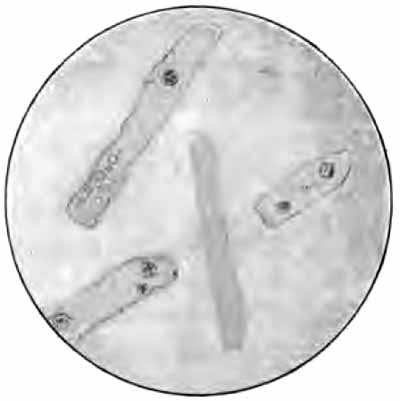

The amount of light is even more important than its direction. It is regulated by the diaphragm. It is always best to use the least light that will show the object well. Unstained objects require very subdued light. Beginners constantly use it too strong. Strong light will often render semitransparent structures, as hyaline casts, entirely invisible (Figs. 2 and 3). Stained objects, especially bacteria, require much greater light.

|   |   |

| FIG. 2.—Hyaline casts, one containing renal cells; properly subdued illumination (from Greene's "Medical Diagnosis"). | FIG. 3.—Same as Fig. 2; strong illumination. The casts are lost in the glare, and only the renal cells are seen (from Greene's "Medical Diagnosis"). |